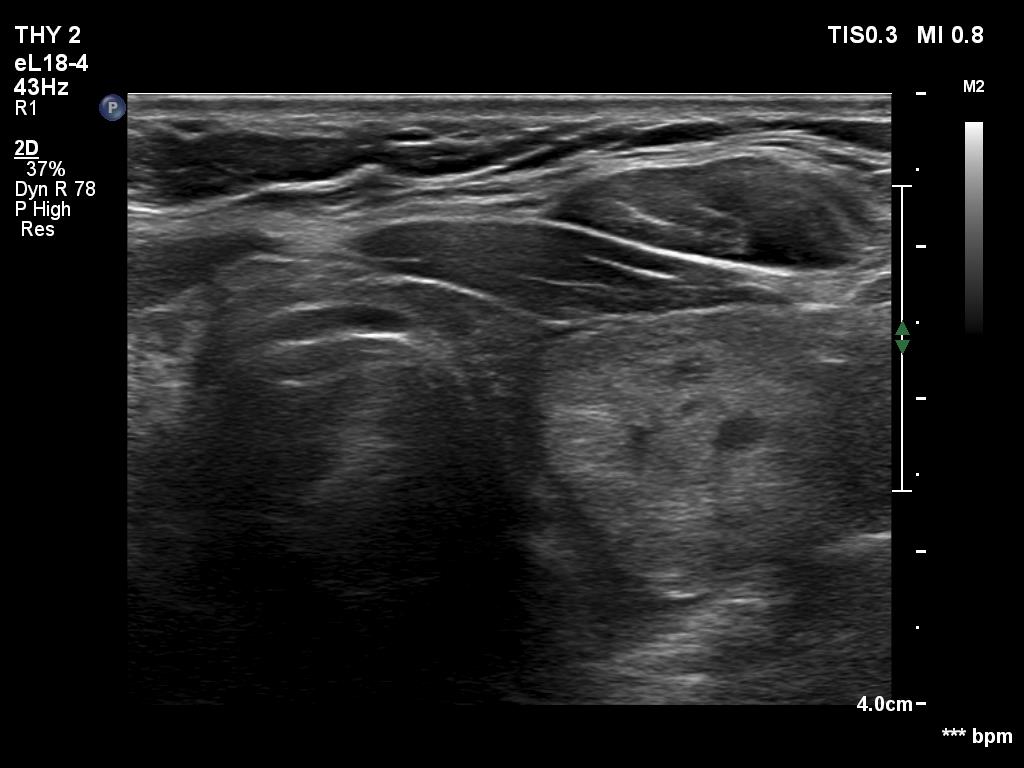

Ultrasonography. The thyroid was hypoechogenic. There was an iso/hyperechoic nodule in both the right and left lobes. The nodule in the left lobe had perinodular vascularity. The dimensions of the nodule in the left lobe were 20x18x31 mm, width, depth, length, respectively. This means that the volume of the nodule has increased almost 8-fold in 10 years.